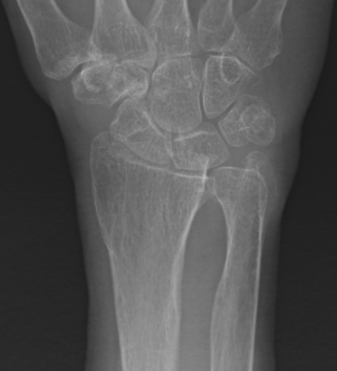

Classification ulna styloid process fractures

| Type 1: Tip fracture | Type 2: Base fracture |

|---|---|

|

Stable DRUJ

DRUJ potentially unstable |

![]() |

Ulna styloid process fracture and acute DRUJ instability

Ulna styloid fracture with TFCC injury